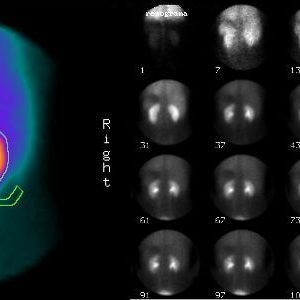

Una gammagrafía ósea implica inyectar una cantidad muy pequeña de material radiactivo (marcador) dentro de una vena. La sustancia viaja a través de la sangre hasta los huesos y órganos. A medida que esta va desapareciendo, emite un poco de radiación. Esta es detectada por una cámara que lentamente escanea el cuerpo.

La cámara gamma detecta las emisiones de energía de la radiosonda en su cuerpo y las convierte en una imágen. La cámara gamma de por sí no emite ninguna radiación. Tiene detectores de radiación denominados cabezas de cámara gamma.